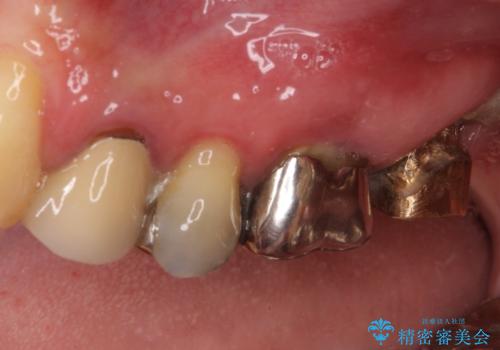

折れてしまった奥歯 インプラントによる補綴治療

- 奥歯に違和感を感じており、抜歯の必要性を感じて来院された患者様です。

診査の結果、5本の奥歯を抜歯してインプラントによる補綴治療が必要と診断されました。

患者様が違和感を感じていない左下の奥歯の治療は今回は見送り、それ以外の治療が必要な奥歯を治療することとしました。